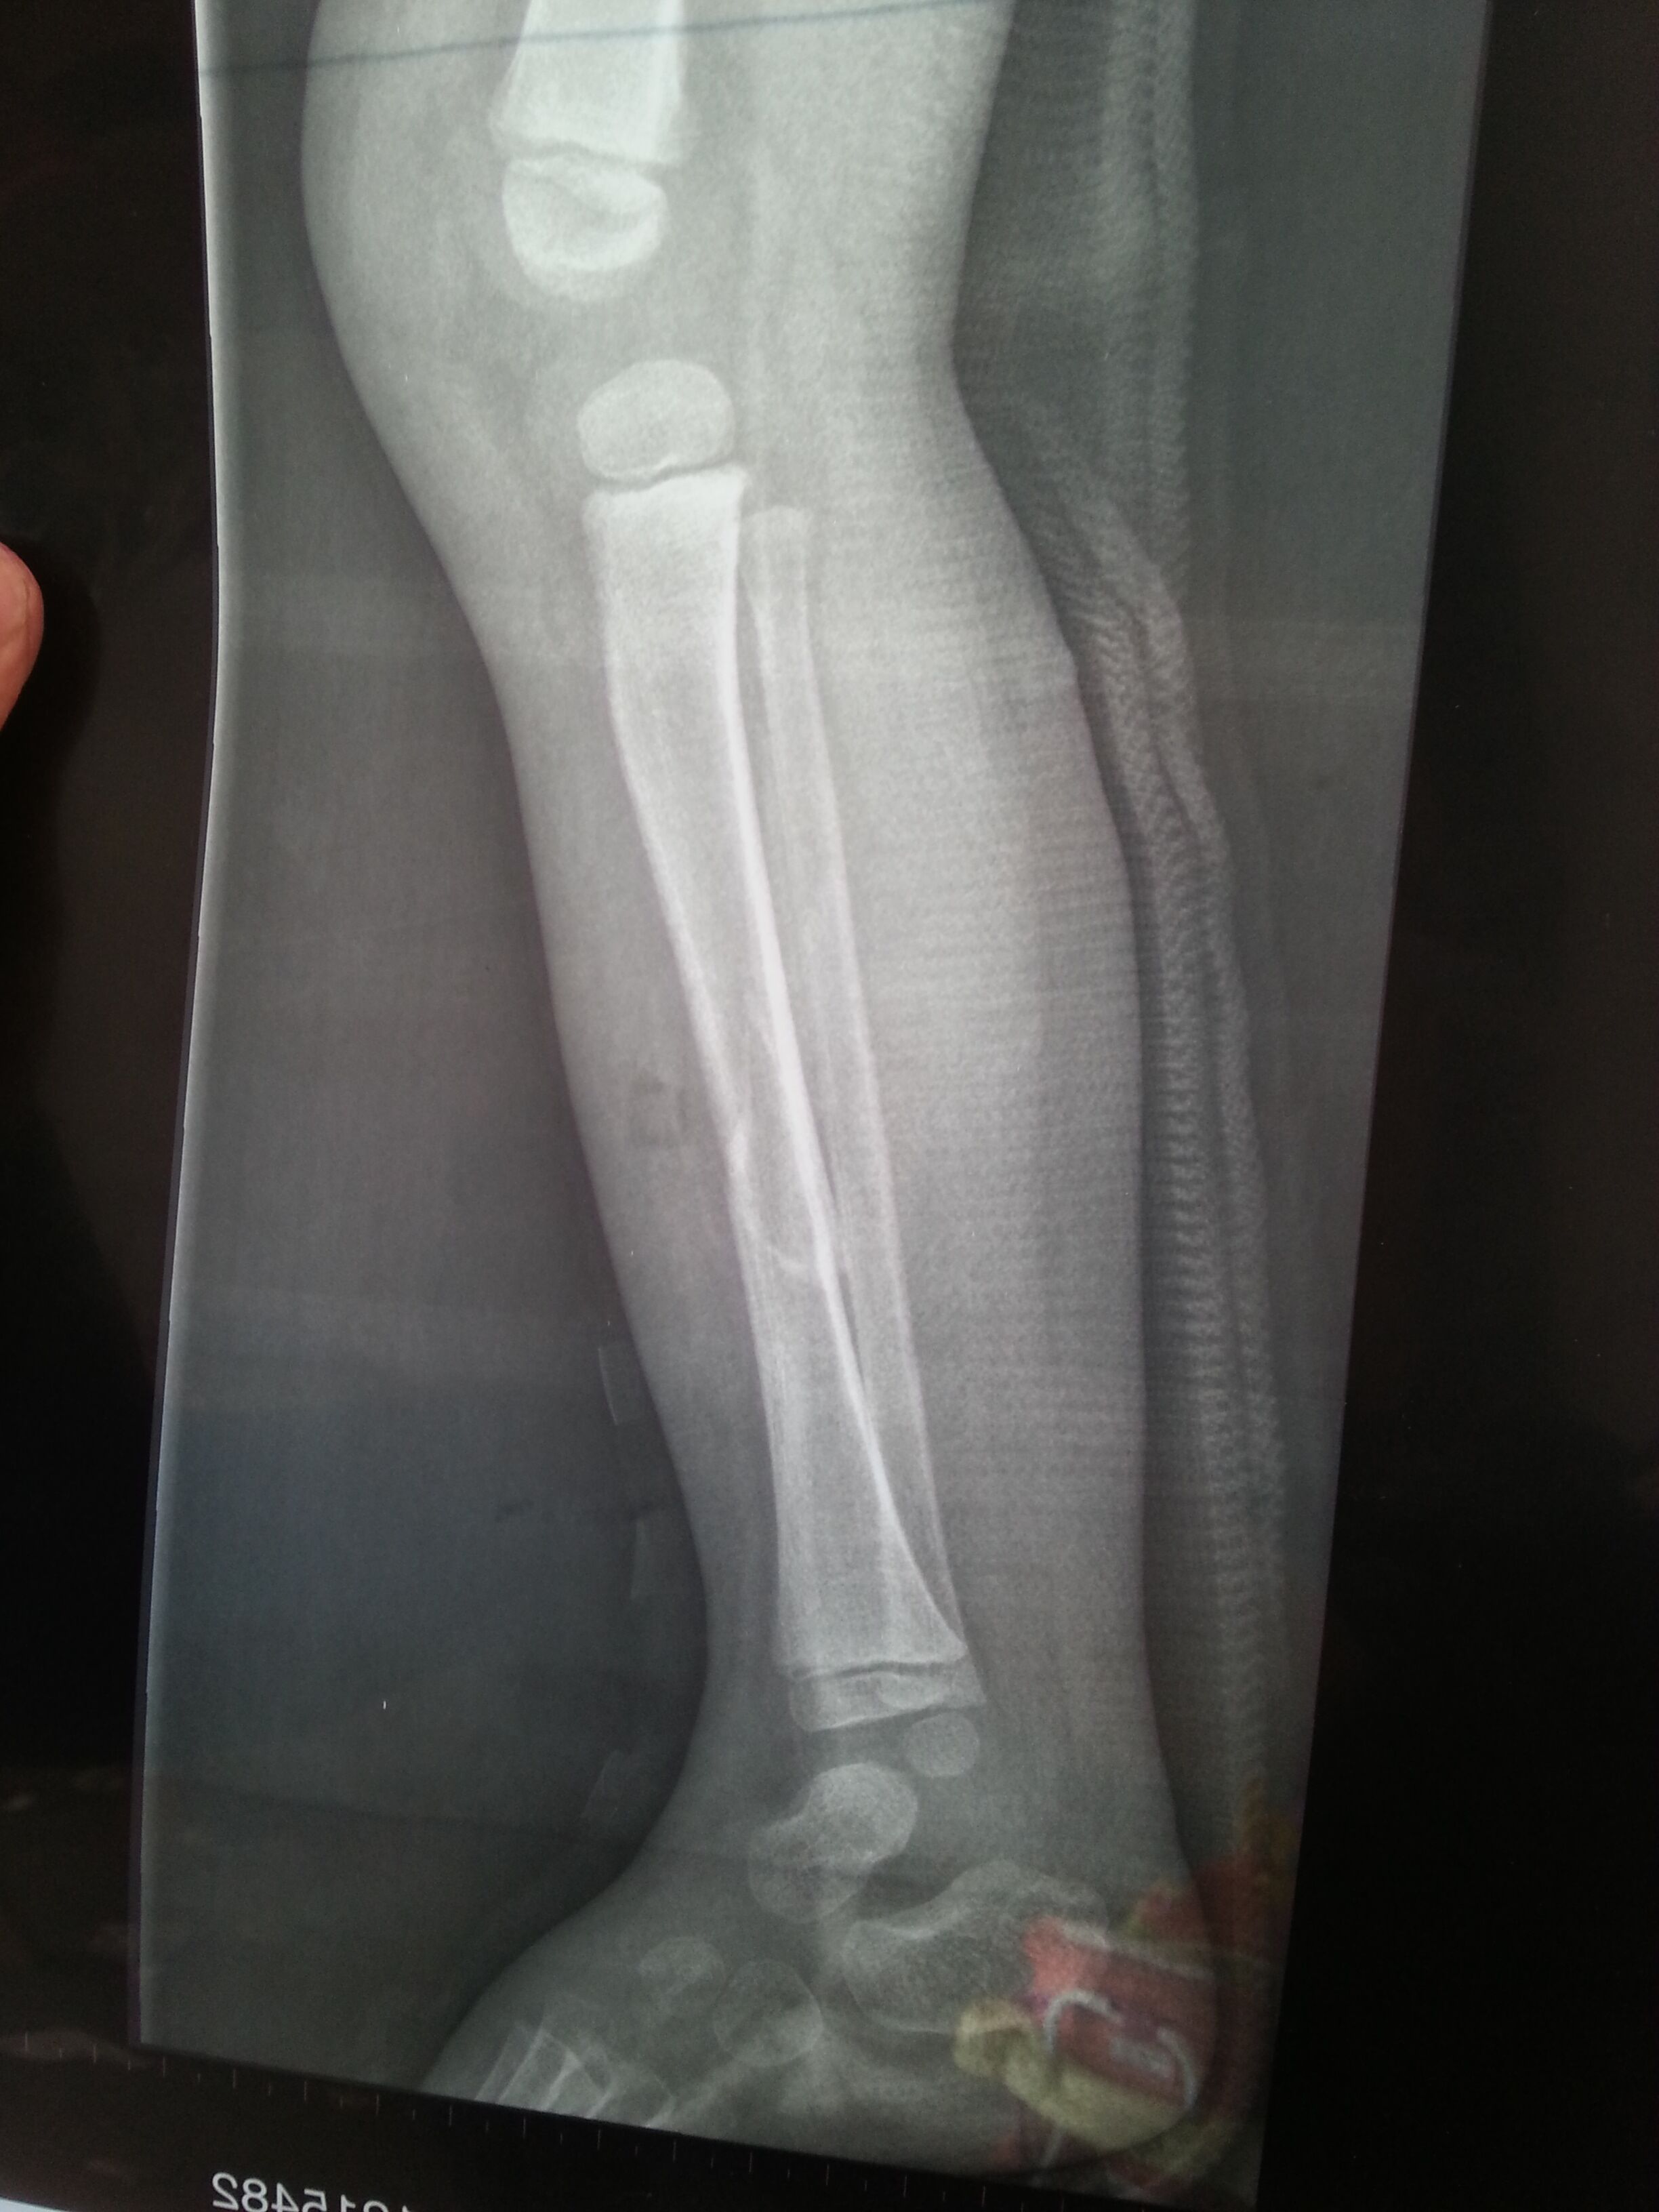

二岁五个月小孩小腿腓骨骨折这样可以长好吗?需要手术吗?怎么治疗比较好?走路会不会点腿?求专家 X片是事后二周拍的 点击展开 匿名用户 2015-03-06 15:49 为您推荐: 其他回答 你好 首先 你家孩子不是腓骨骨折,是胫骨骨折!!其次,这个骨折是斜形骨折,非稳定性骨折,所以错位很明显,而且中间还有蛮大的缝隙。这是需要手术的,如果就这么让他长,胫骨一个有可能长不好,还一个就是长好也是畸形的。建议手术治疗!! zhoubotong8046 2015-03-06 16:42 相关问题 小腿腓骨骨折五个月了还不能走路,这是正常的吗? 小腿左胫腓骨骨折,需要多长时间能走路? 小腿胫腓骨骨折多久能走路啊